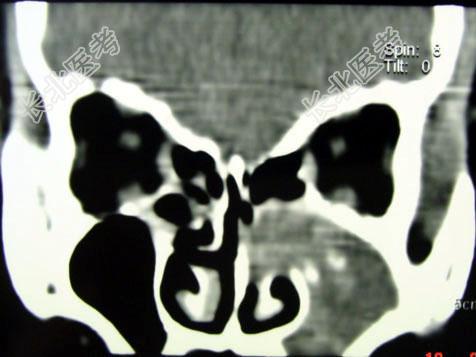

- 单项选择题男,41岁, 左侧鼻腔胀痛半年余,CT检查如图, 最可能的诊断是 ( )

A、出血坏死性息肉

B、化脓性鼻窦炎

C、过敏性鼻窦炎

D、真菌性鼻窦炎

E、上颌窦癌